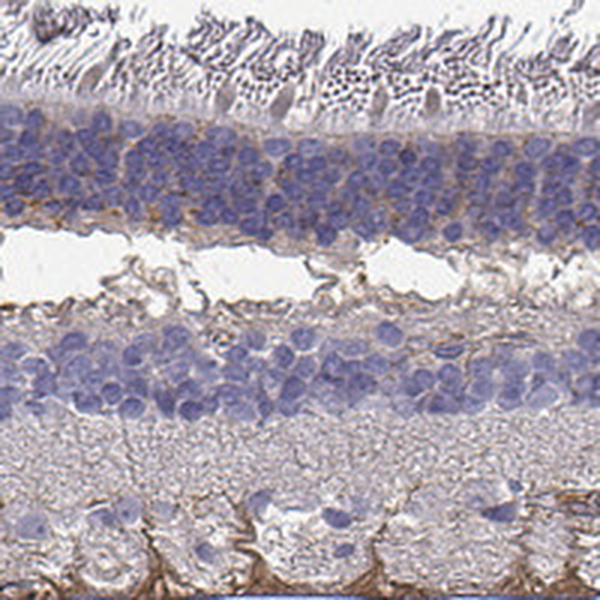

Immunohistochemical staining of human retina shows moderate cytoplasmic positivity in nerve fiber layer.